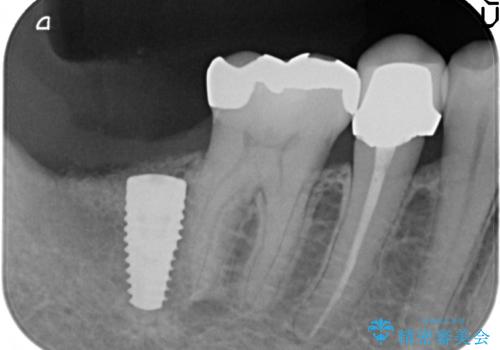

- 右下7番にインプラント治療を行った症例です。

CT撮影を行い状態を確認後、インプラント(ストローマン)の埋入(一次手術)を行いました。

インプラントと骨の定着を待った後に二次手術を行い、カスタムアバットメント、オールセラミッククラウンによる補綴を行いました。